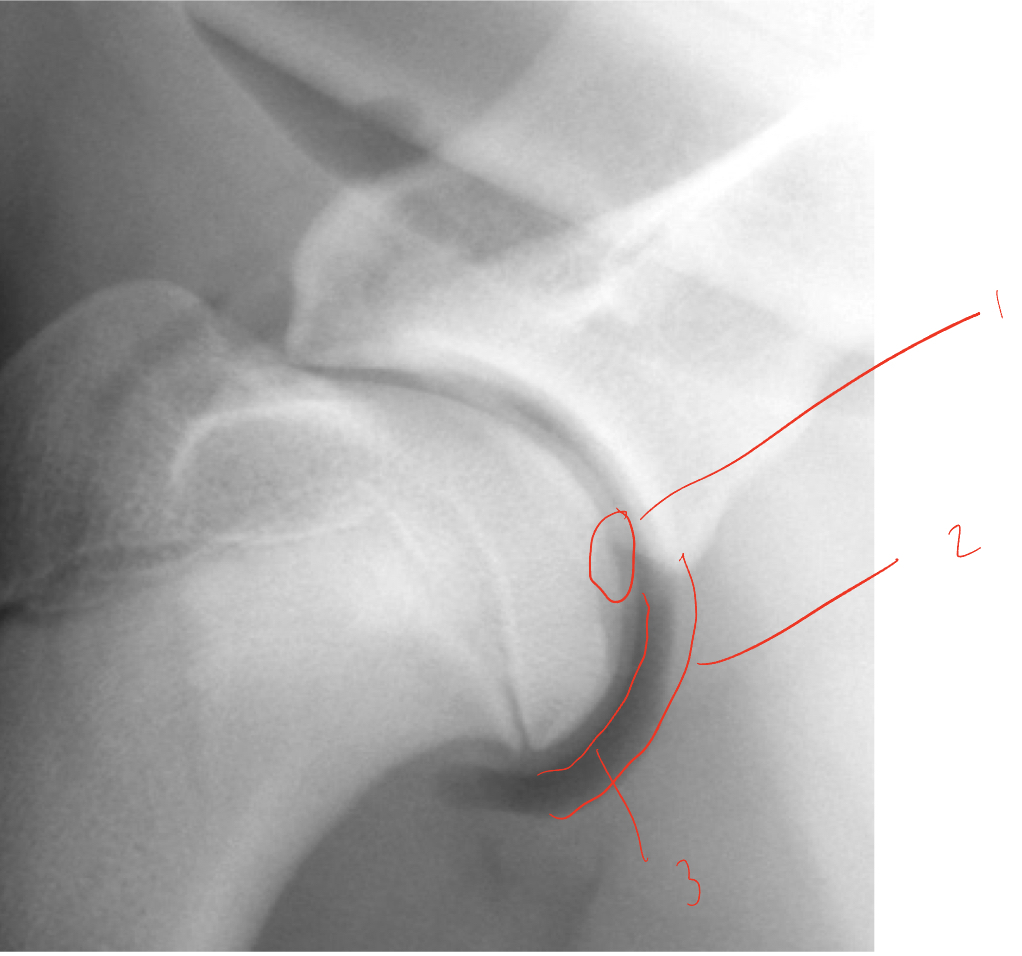

injected air to better visualize articular cartilage- identify 1-3

1. OCD

2. Joint capsule

3. Articular cartilage